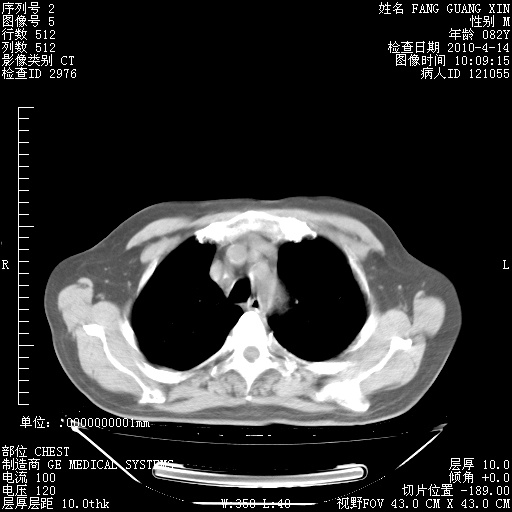

4月14日肺部CT

23.JPG

24.JPG

25.JPG

26.JPG

肺部CT平扫未见异常。